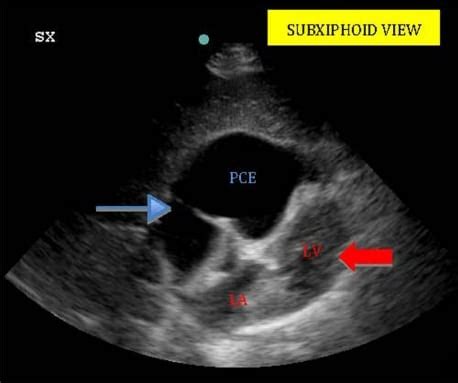

This type contains cancer cells, seen in people with lung cancer, breast cancer, or other metastases to the lung.besides pleurodesis, thoracentesis is an option, with placement of a stent (indwelling pleural catheter or tunneled pleural catheter) to continually drain the fluid. The aetiology of the pleural effusion determines other signs and symptoms. A large pericardial effusion >20 mm with concomitant pleural effusion is also evident posteriorly to the aorta. Nov 04, 2020 · malignant pleural effusion: A word from verywell a pericardial effusion may be mild and temporary with conditions such as some viral infections, but can be serious and a poor prognostic sign for people living with cancer. Mar 31, 2020 · better treatment options for metastatic cancer as well as prompt treatment of a developing pericardial effusion are critical to improve survival. May 25, 2021 · pleural effusion predominantly presents with breathlessness, but cough and pleuritic chest pain can be a feature. Diagnostic tests are indicated to document the presence of pleural fluid and to determine its cause (see figure diagnosis of pleural effusion).